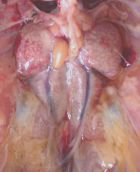

نشانیها : کیسه هایی هوایی ضخیم میشود و ترشحات پنیری شکل دیده میشود . اغلب همراه با آن پریکاردیت چسبنده ایجاد میشود . تشخیص با استفاده کشت میکروبی قطعی میشود

درمان :رعایت بهداشت در گله و جلوگیری از استرس در پیشگیری موثر است .کلرامفنیکل ٬فورازولیدون در درمان آن موثر است ولی توصیه می گرددکشت میکروبی و آنتی بیوگرام انجام گردد